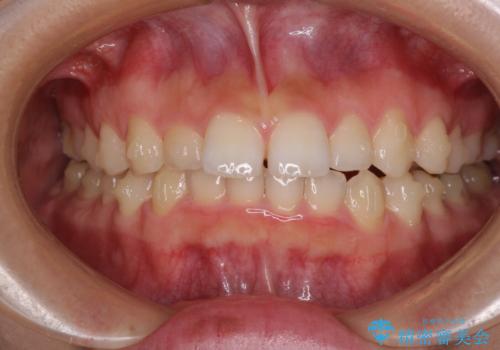

前歯のデコボコと突出感 インビザラインによる矯正治療

- 上下前歯のデコボコと、上顎前歯の突出感を気にして来院された患者様です。

インビザラインによる上下歯列の側方拡大と後方移動、IPR(歯と歯の間を削る)にるスペースの獲得により歯列を整えることとしました。

毎日22時間以上しっかりとマウスピースを装着していただいたので、スムーズに治療が進みました。歯と歯の間を削ることでうまくスペースコントロールでき、1年強で終えることができました。